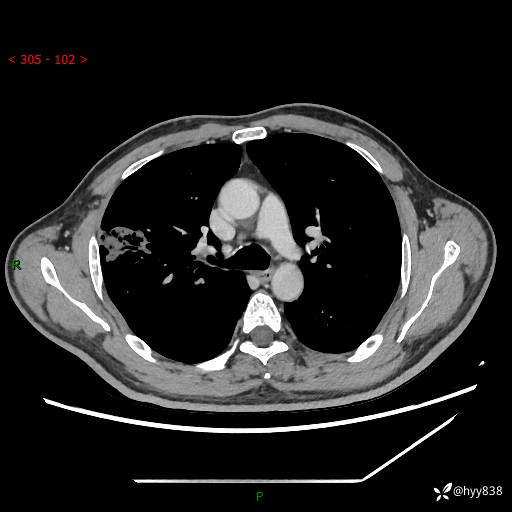

性别:男

年龄:47岁

现病史:患者2天前体检完善胸部CT提示:右上肺团块影,炎症可能,肿瘤性病变不除外,冠状动脉钙化,无咳嗽、咳痰,无寒战发热,无恶心、呕吐等其他特殊不适,未予以特殊治疗,现为明确病变性质来我院就诊,门诊以“肺肿物性质待查”收入我科。 起病以来,患者精神、饮食、睡眠可,大小便正常,体力体重较前无明显变化。

胸部CT平扫+增强